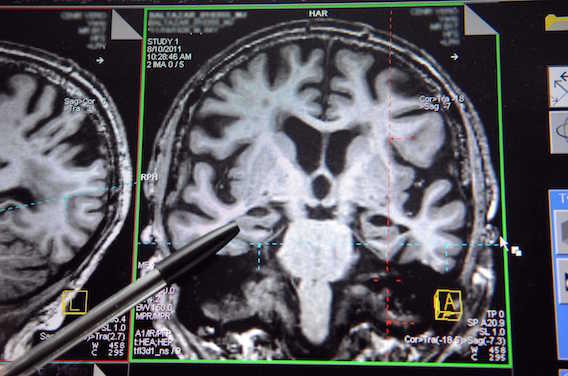

Les travaux de l’équipe de John Collinge et Sebastian Brandner, publiés ce jeudi dans la revue Nature, pourraient marquer un tournant dans la compréhension de la maladie d’Alzheimer. Les chercheurs britanniques y démontrent, pour la première fois chez l’homme, que le développement de la maladie neurodégénérative pourrait être déclenché par des protéines exogènes ; il pourrait donc exister une certaine forme de transmission de la maladie.

Les travaux britanniques viennent cependant confirmer chez l’homme, une hypothèse que Mathias Jucker avait lui-même échafaudée, sur la base de travaux menés chez des souris.

« Mathias Jucker a montré que des souris auxquelles on avait injecté des extraits de cerveau de patients atteints d’Alzheimer, pouvaient développer, au bout d’un certain temps, des plaques amyloïdes », rappelle le Pr Philippe Amouyel, directeur général de la Fondation Plan Alzheimer.

L’injection de fragments de protéines amyloïdes – des « graines » – pourrait donc déclencher une réaction en chaîne, similaire à ce que l’on observe dans les maladies dites « à prions », telles que la maladie de Creutzfeldt-Jakob. Au contact de ces « graines », la structure des protéines saines serait modifiée, entraînant à terme la formation de plaques.

Autopsie de 8 cerveaux

Les chercheurs britanniques sont parvenus, cette fois-ci, à des conclusions similaires chez l’homme. Pour cela, ils ont analysé le cerveau de huit patients décédés des suites de la maladie de Creutzfeldt-Jakob, après avoir été traités avec de l’hormone de croissance. Or à cette époque, l’hormone de croissance n’était pas encore synthétique, mais extraite de cerveaux de cadavres.

Chez quatre des huit patients, les scientifiques ont été surpris de découvrir des dépôts de protéines amyloïdes, semblables à ceux qui surviennent dans la maladie d’Alzheimer. Or ces patients étaient trop jeunes pour être déjà atteints de la maladie. De plus, il n’y avait dans ces cerveaux aucune anomalie des protéines Tau, pourtant caractéristique de la maladie d’Alzheimer.

« Il est donc possible que les extraits des cerveaux avec lesquels ces patients ont été traités aient contenu des « graines » d’amyloïde », explique Philippe Amouyel.

Ces travaux ne montrent cependant pas un caractère transmissible de la maladie, mais au mieux, des protéines amyloïdes, sources de plaques. « La maladie d’Alzheimer n’est pas contagieuse », insistent les auteurs de l’étude, qui soulignent que jusqu’ici, aucune étude épidémiologique n’a suggéré un risque de transmission, par transfusion sanguine, notamment.

Cependant, ils rappellent aussi que les « graines d’amyloïde » adhèrent sur les instruments en métal, et résistent aux protocoles standard de stérilisation. Des données qui pourraient amener à reconsidérer le risque de propagation des ces protéines.